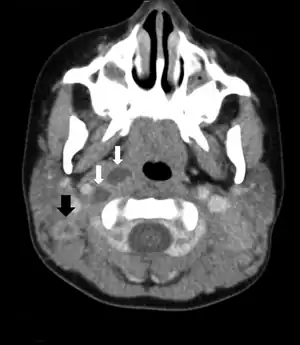

Cervical lymphadenitis caused by Mycobacterium florentinum